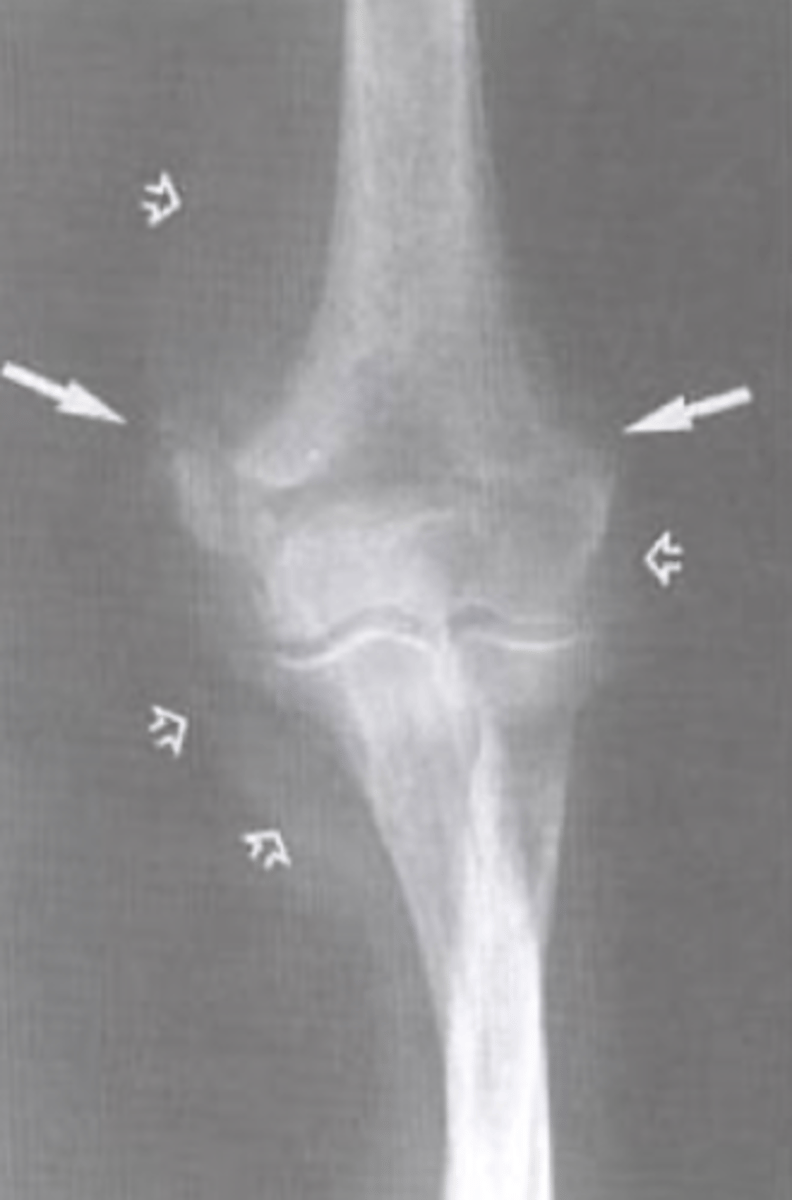

positive fat pad sign

What is the issue?